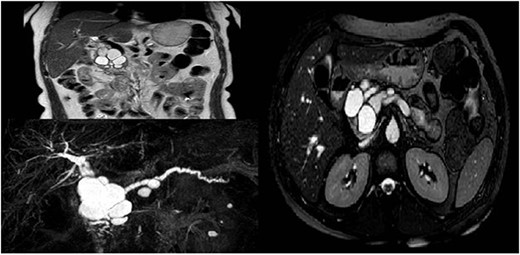

Measurement of the oncomarkers showed a CA 19.9 value of 343 U/ml (normal < 40). Following the ERCP, the patient was submitted to further investigations with MRI and EUS. The MRI with cholangiographic sequences revealed a cystic cluster, with maximum diameter of 3 cm in the pancreatic head, responsible for the biliary compression (Fig. 1).

Radiological features of a large complex cyst of the pancreatic head.